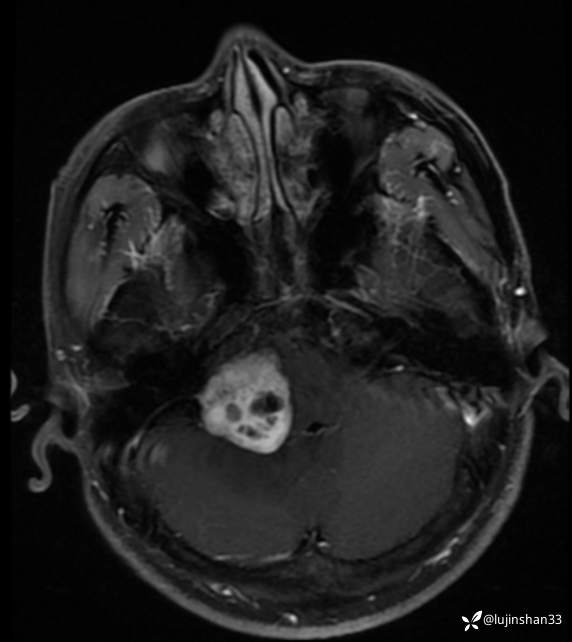

术前CT及MRI

术后病理示:(右侧桥小脑角)考虑为血管母细胞瘤,WHO?1级,术中及术后送检组织大小分别为0.6x0.5x0.3cm,2.5x2.5x0.6cm。免疫组化结果:CD34(血管+),S-100(部分+),Inhibin-α(+),CAⅨ(+),Ki-67(+5%),NSE(部分+),EMA(-),Vimentin(+),CD56(+),VEGF(+),GFAP(部分+),D2-40(部分+),Olig-2(-)。特殊染色结果:网织纤维染色(+)。补充诊断:免疫组化结果:CD10(-),PR(-),CD68(小灶+),SSTR2(-)。术

临床诊断:右侧桥小脑角血管母细胞瘤